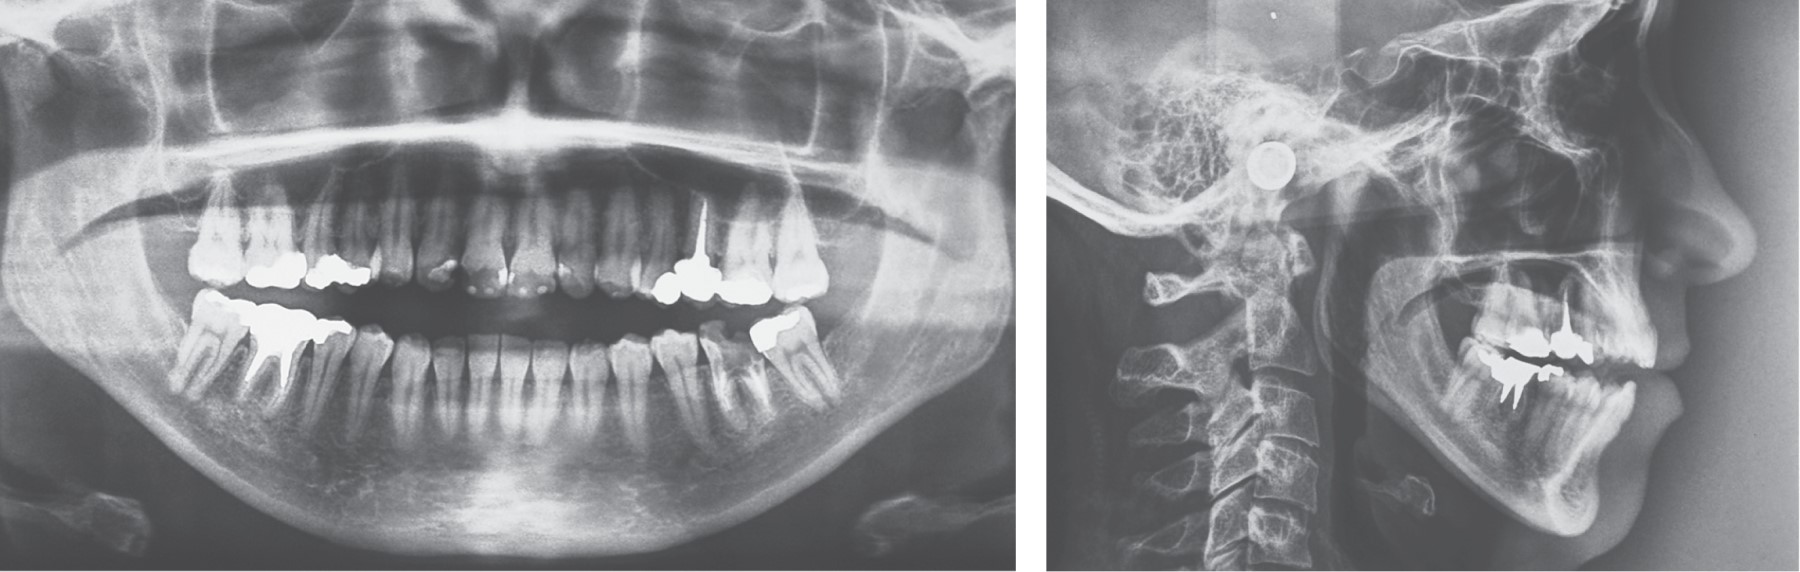

Introduction: the objective is to present a case of total alloplastic replacement of the temporomandibular joint with personalized prostheses (TMJ Concepts®) in rheumatoid arthritis and injection of botulinum toxin type A for protection of prostheses against bruxism. Clinical case: we present the case of a 44-year-old female patient with severe bilateral temporomandibular joint (TMJ) resorption due to advanced stages of rheumatoid arthritis, which was managed by total replacement with a personalized alloplastic prosthesis (TMJ Concepts®, Ventura CA) and infiltration of botulinum toxin type A (Botox, Allergan, Ireland). Results: painful symptomatology was eliminated immediately and pre-surgical oral opening changes from 2 to 50 mm were achieved in the first year after botulinum toxin placement; 12 years later, the prosthesis is stable and functional. Conclusions: botulinum toxin can be a simple, safe, and effective adjuvant treatment in patients reconstructed with personalized alloplastic prostheses.

Figure 5

Figure 6